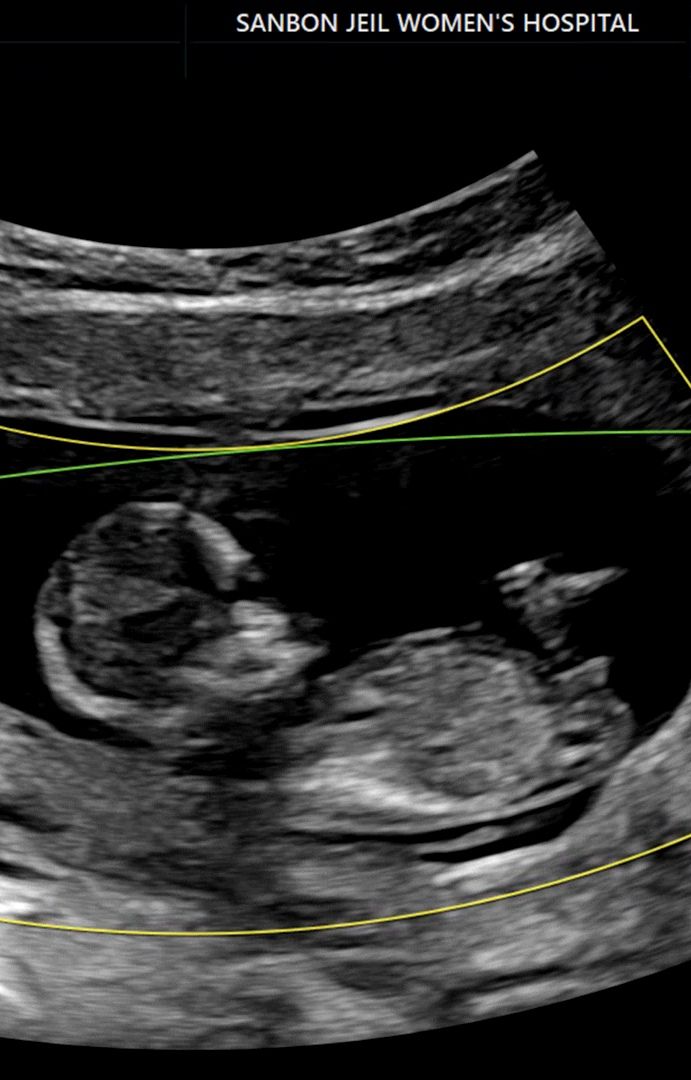

각도법 초음파 봐주세욤 ! 🩷🎉

저는 사실 잘볼줄몰라요ㅠㅠ 부탁드려요!🩷

딸이네요 ㅎㅎ